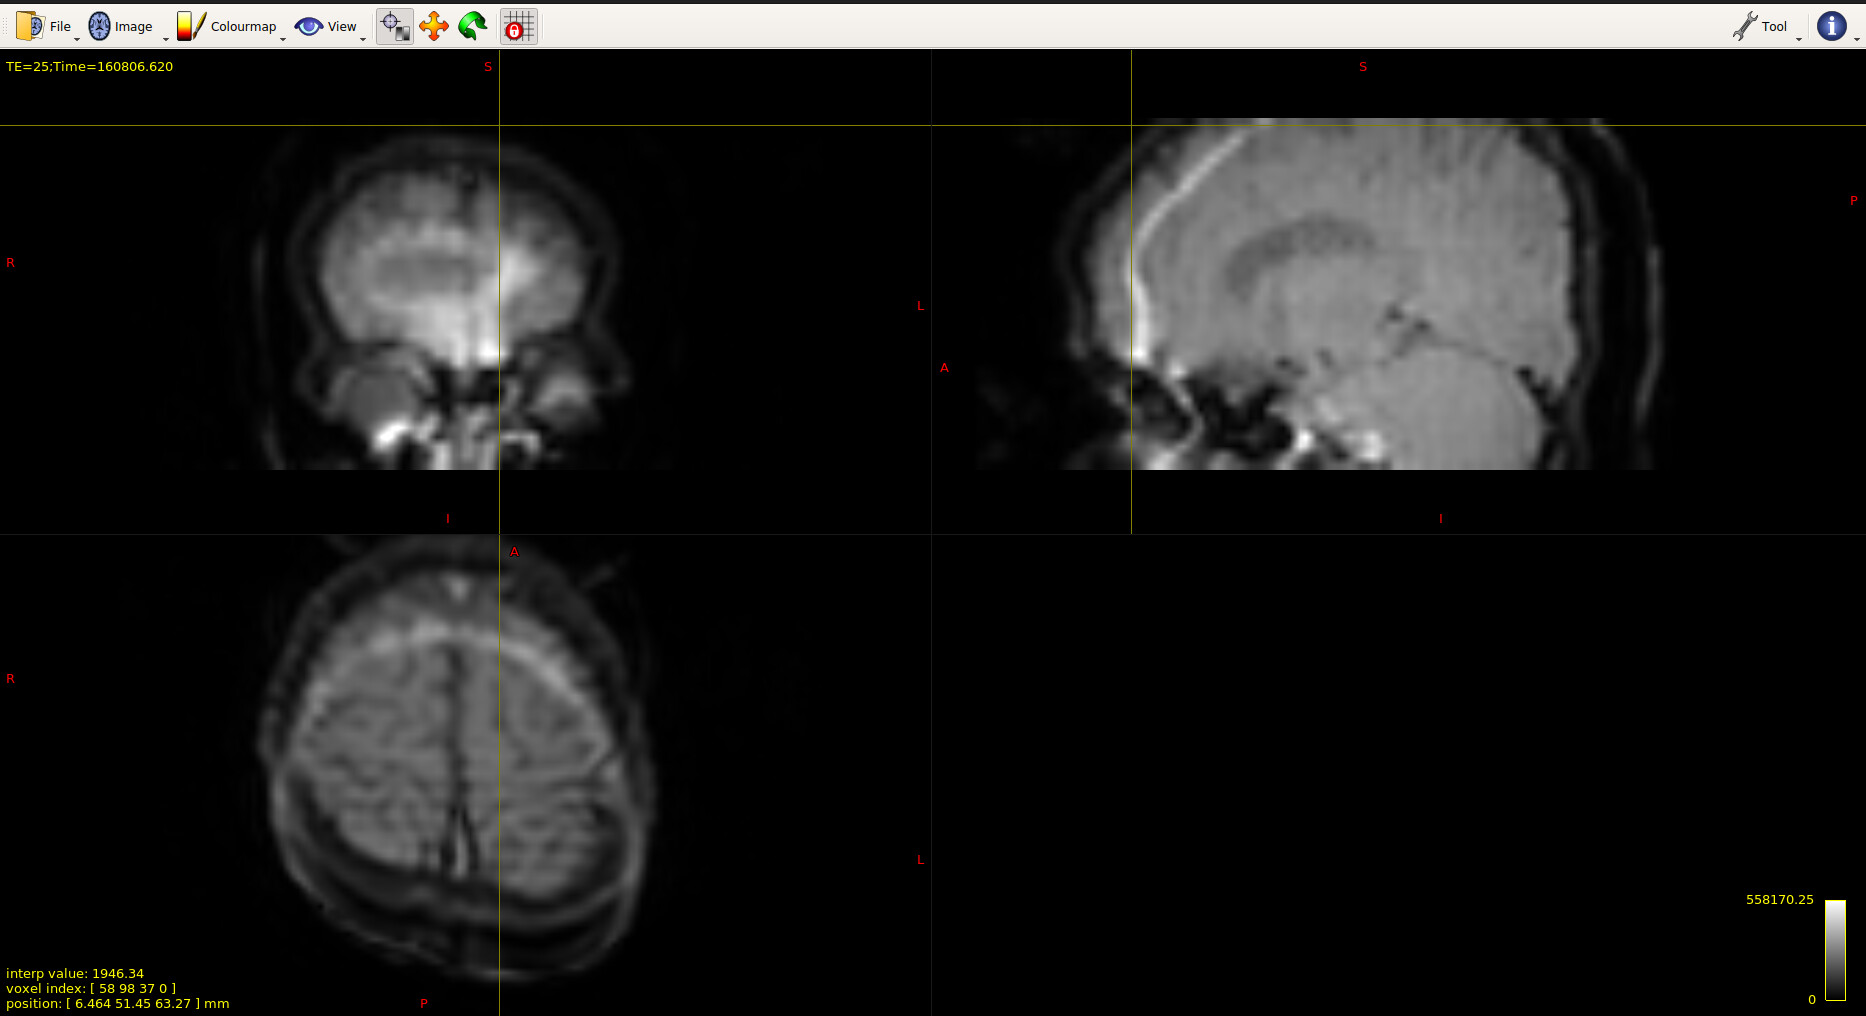

I am Samuel and I am quite new to the domain. In some of the fMRI images that was provided to me, there were some ring or ghosting like artefacts. Could someone help me with understanding the reason behind it and is there an tool which can be used to remove this artefact? I have attached the image below for reference. This is a resting state fMRI and subjects were sedated during the entire procedure (TR = 1.7).